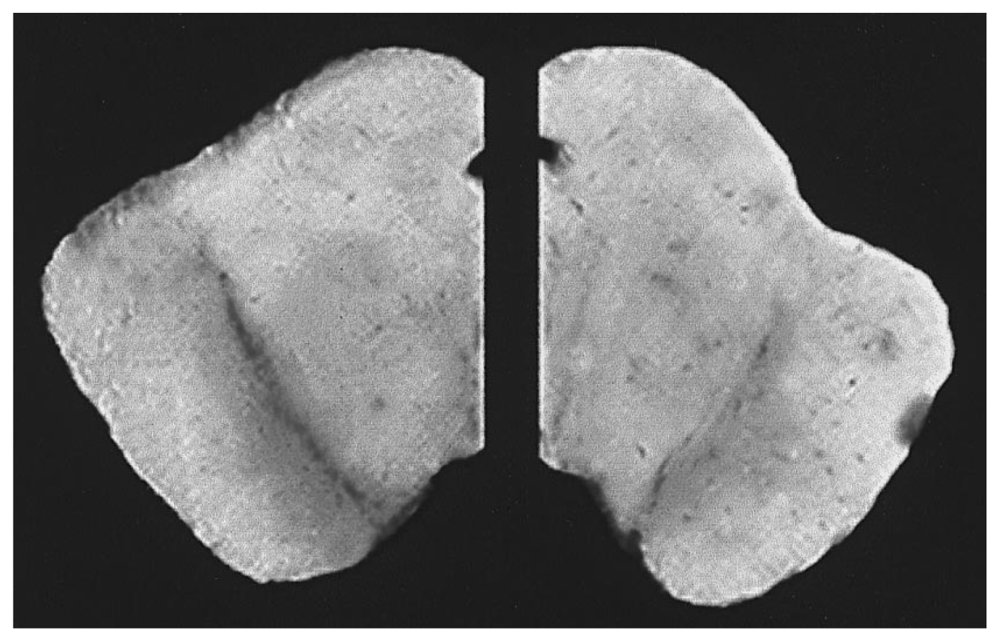

- Frey, KA; Koeppe, RA; Kilbourn, MR; van der Borght, TM; Albin, RL; Gilman, S; Kuhl, DE. Presynaptic monoaminergic vesicles in Parkinson’s disease and normal aging. Ann. Neurol 1996, 40, 873–884. [Google Scholar]

- Brownell, AL; Jenkins, BG; Isacson, O. Dopamine imaging markers and predictive mathematical models for progressive degeneration in Parkinson’s disease. Biomed. Pharmacother 1999, 53, 131–140. [Google Scholar]